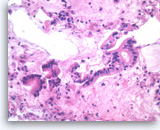

Solid pseudopapillary tumor,

Pancreas FNA, Cell Block.

The tumor shows pseudopapillae with hyalinized fibrovascular cores lined by several layers of bland epithelioid cells.

20X

Solid pseudopapillary tumor,

Pancreas FNA, Cell Block.

The tumor shows pseudopapillae with hyalinized fibrovascular cores lined by several layers of bland epithelioid cells.

20X